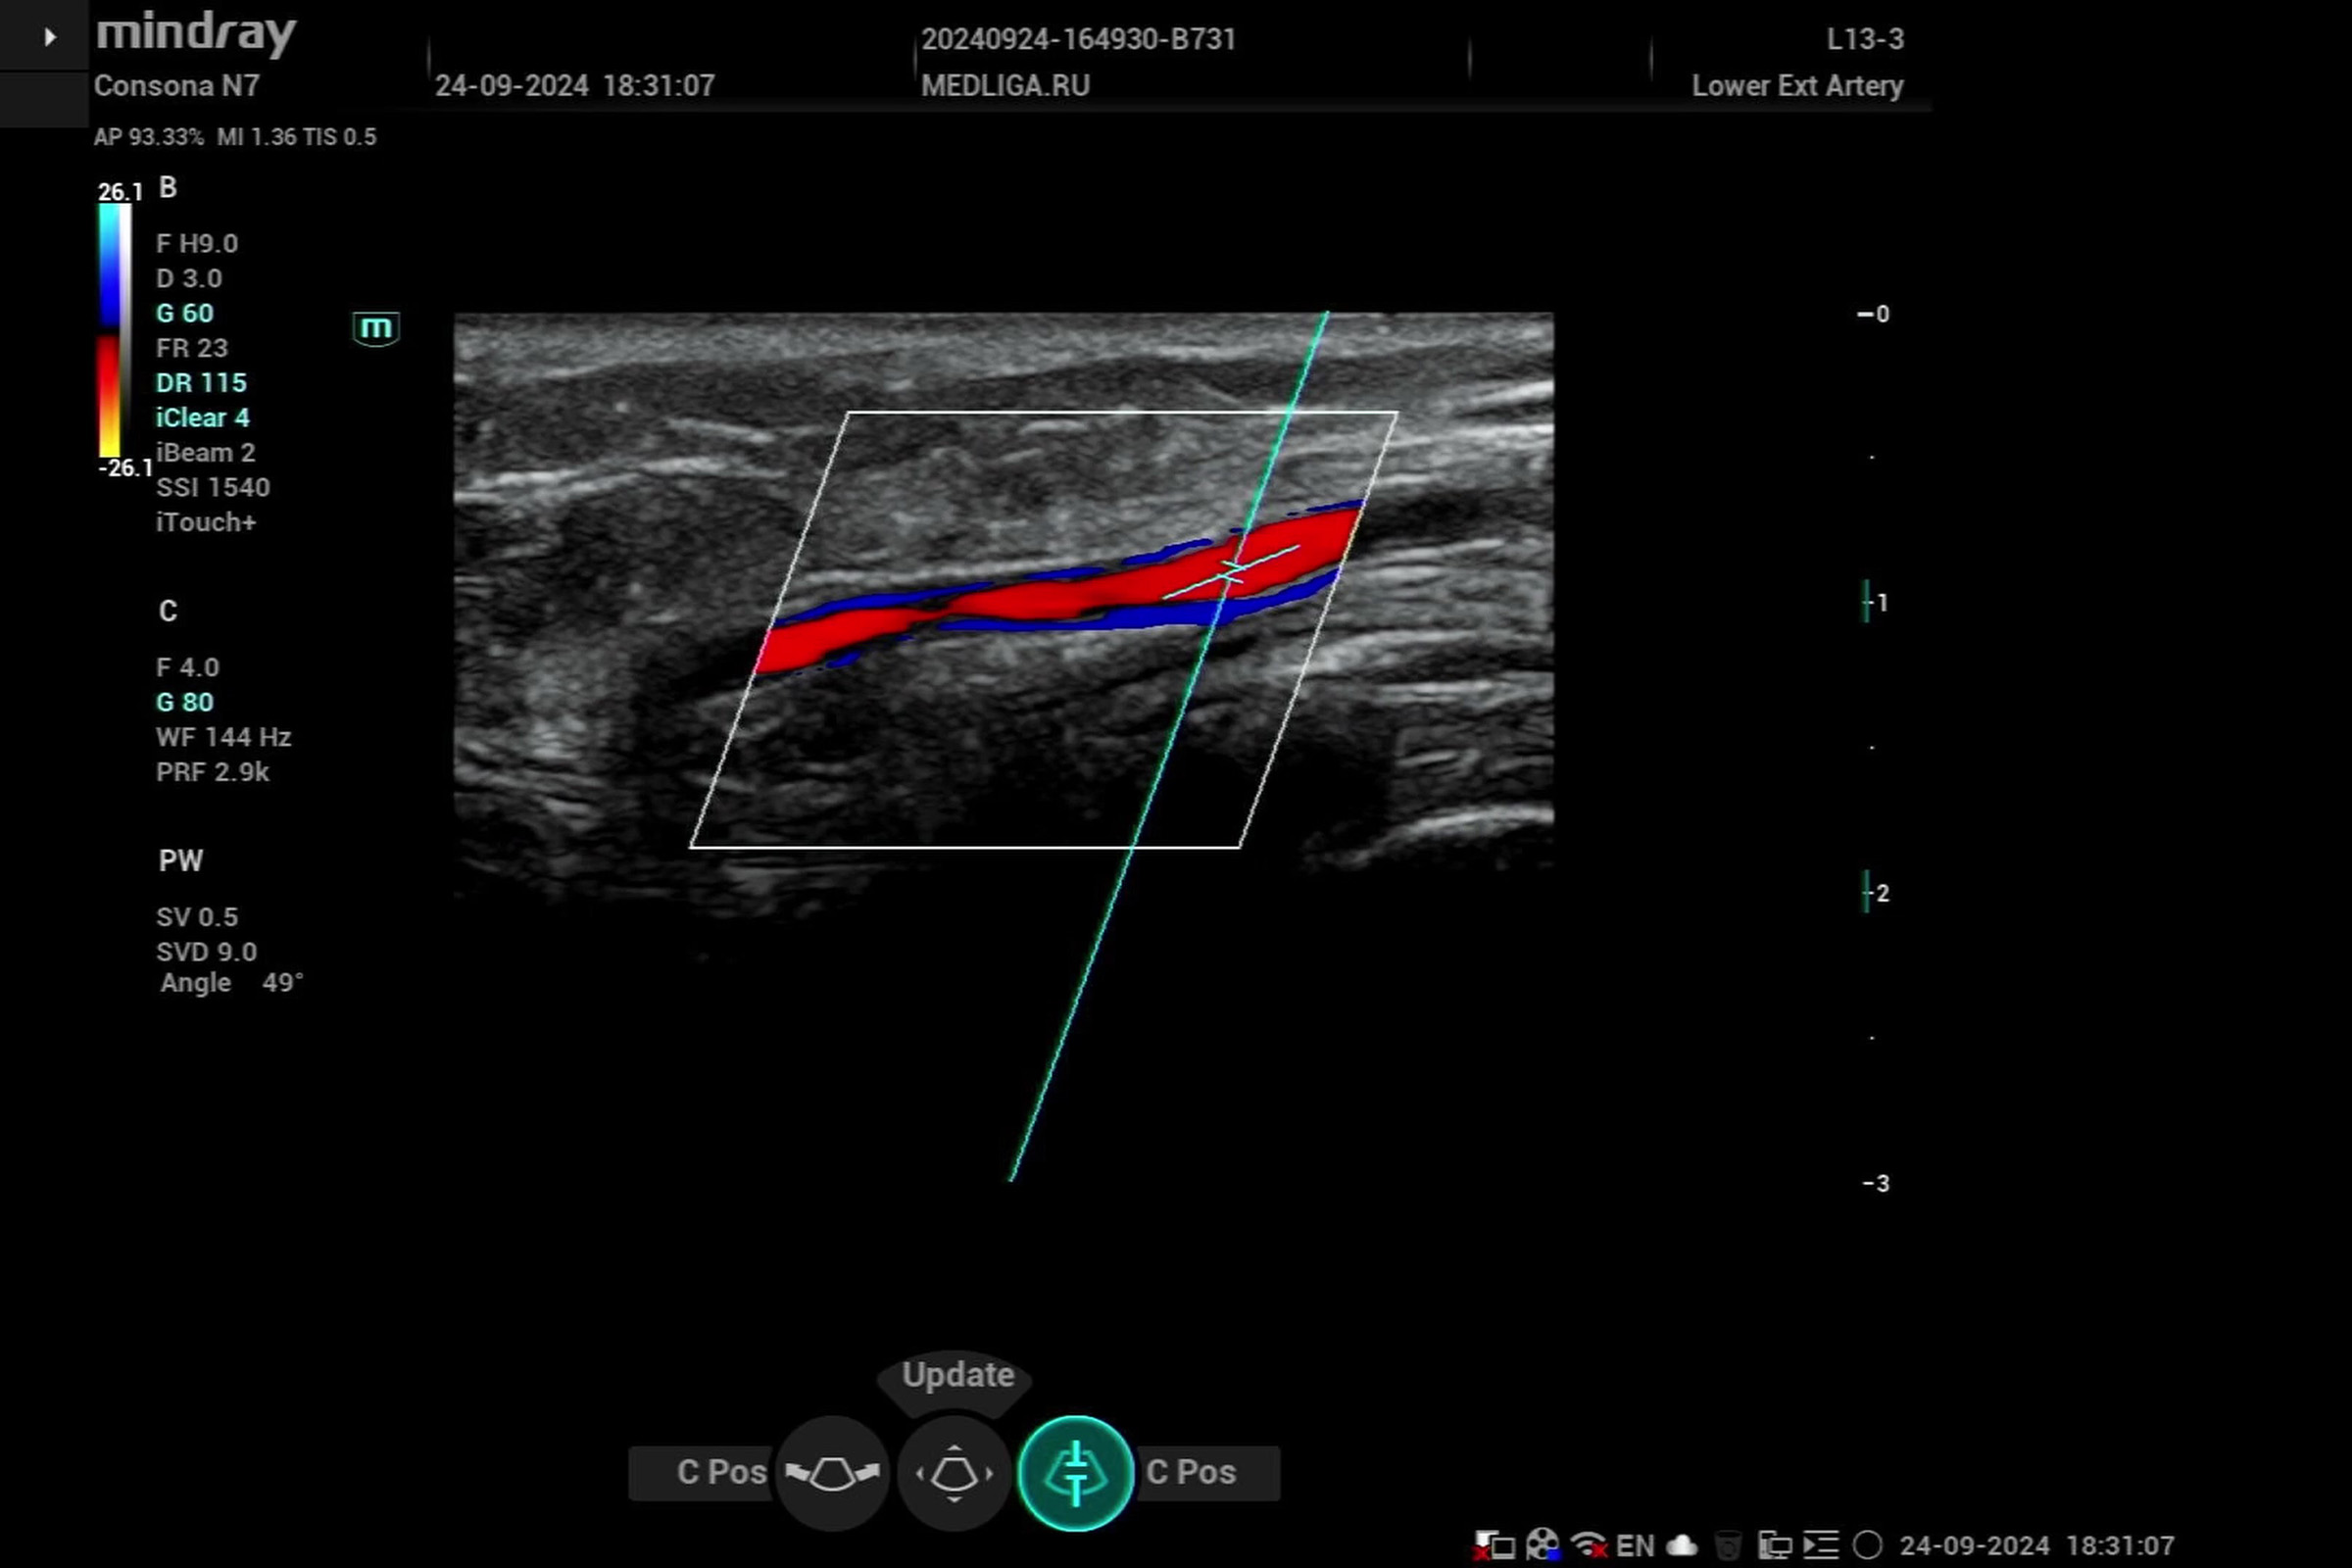

Видео узи артерий

Видео узи артерий 107 фото